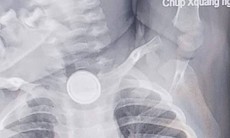

Dị vật sau khi được gắp ra. Ảnh: BVCC.